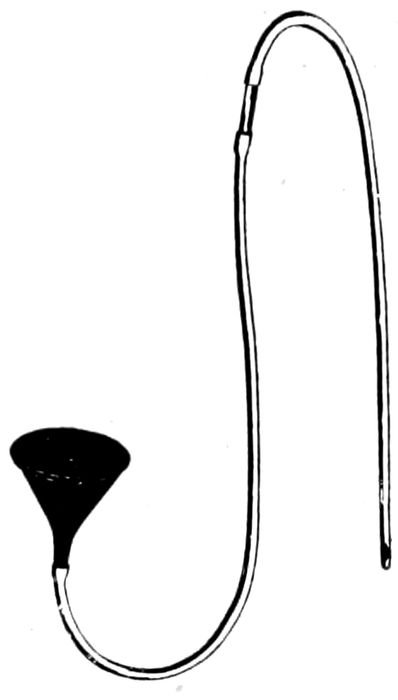

| 122. |

Apparatus for gavage or lavage |

286 |

| |